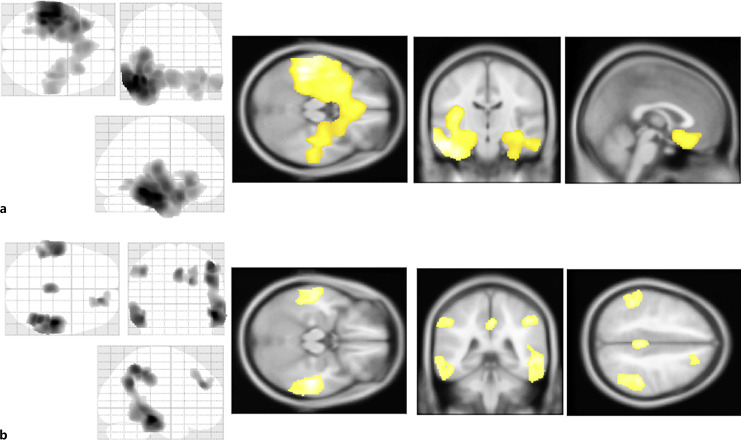

Results: Compared to the EOAD group, the LOAD group had significantly higher scores on orientation in place. Compared to the LOMCI patients, the EOMCI patients achieved significantly higher recall scores. The LOAD and LOMC groups showed significant volume reductions in bilateral medial temporal regions compared to the HCs. The EOAD and EOMCI groups did not show significant atrophy of the medial temporal region compared to the HC group.

Conclusions: The hippocampal volume and memory were preserved in the patients with EOMCI or EOAD compared to those with LOMCI or LOAD. These findings may indicate that the distinct and differing patterns of neuropsychological changes between EOAD and LOAD are also common in MCI, which is intermediate between normal cognition and AD.